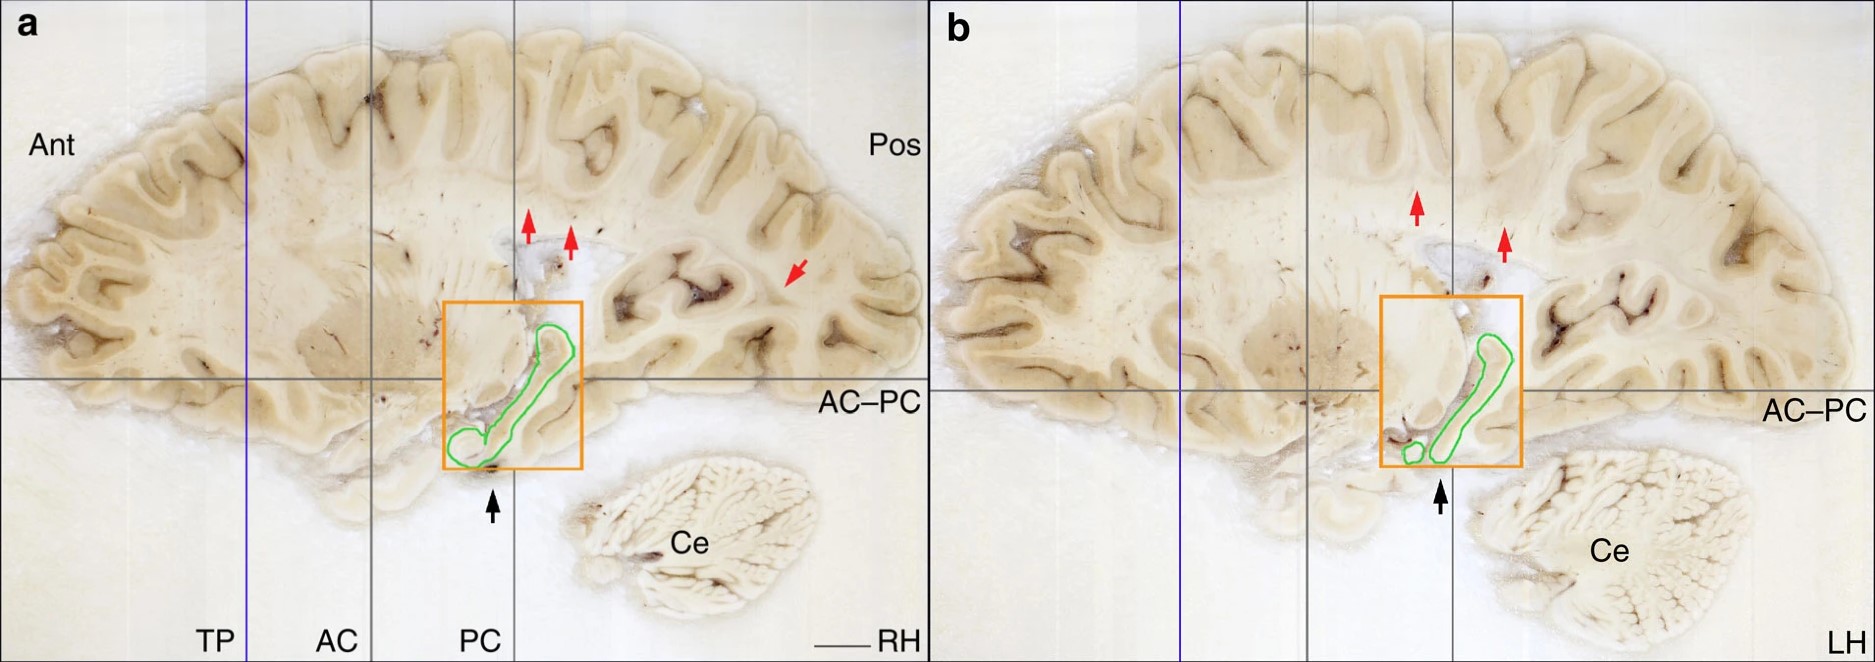

Срезы правого (a) и левого (b) полушарий мозга Г.М. Оранжевый прямоугольник ограничивает часть неповрежденного гиппокампа (выделена зеленым). Изображение из статьи J. Annese et al., 2014. Postmortem examination of patient H.M.’s brain based on histological sectioning and digital 3D reconstruction